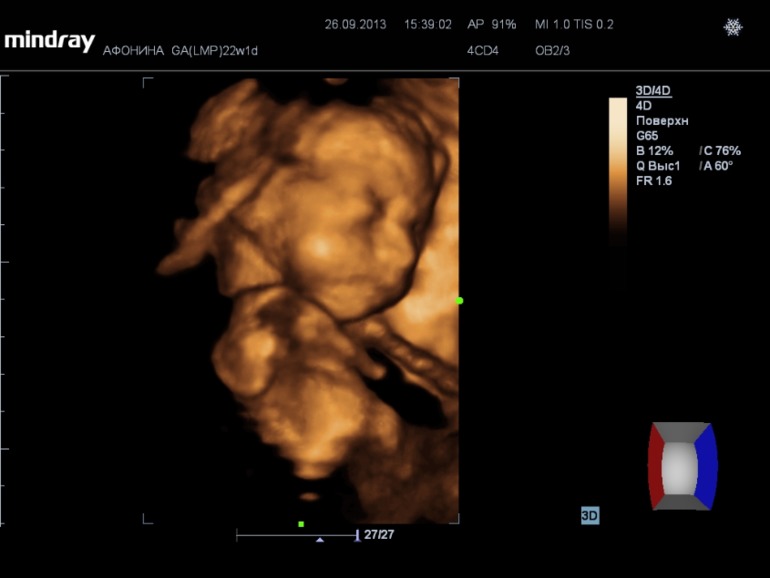

На 3d нам сказали что ребеночек ну очень щекастый, нос картошкой))) Наделали кучу фото и видео (запись на диск 300р), насмотрелись вдоволь. А в самом конце нам сказали пол.....

А вот и фото нашей принцессы))) (под кат)